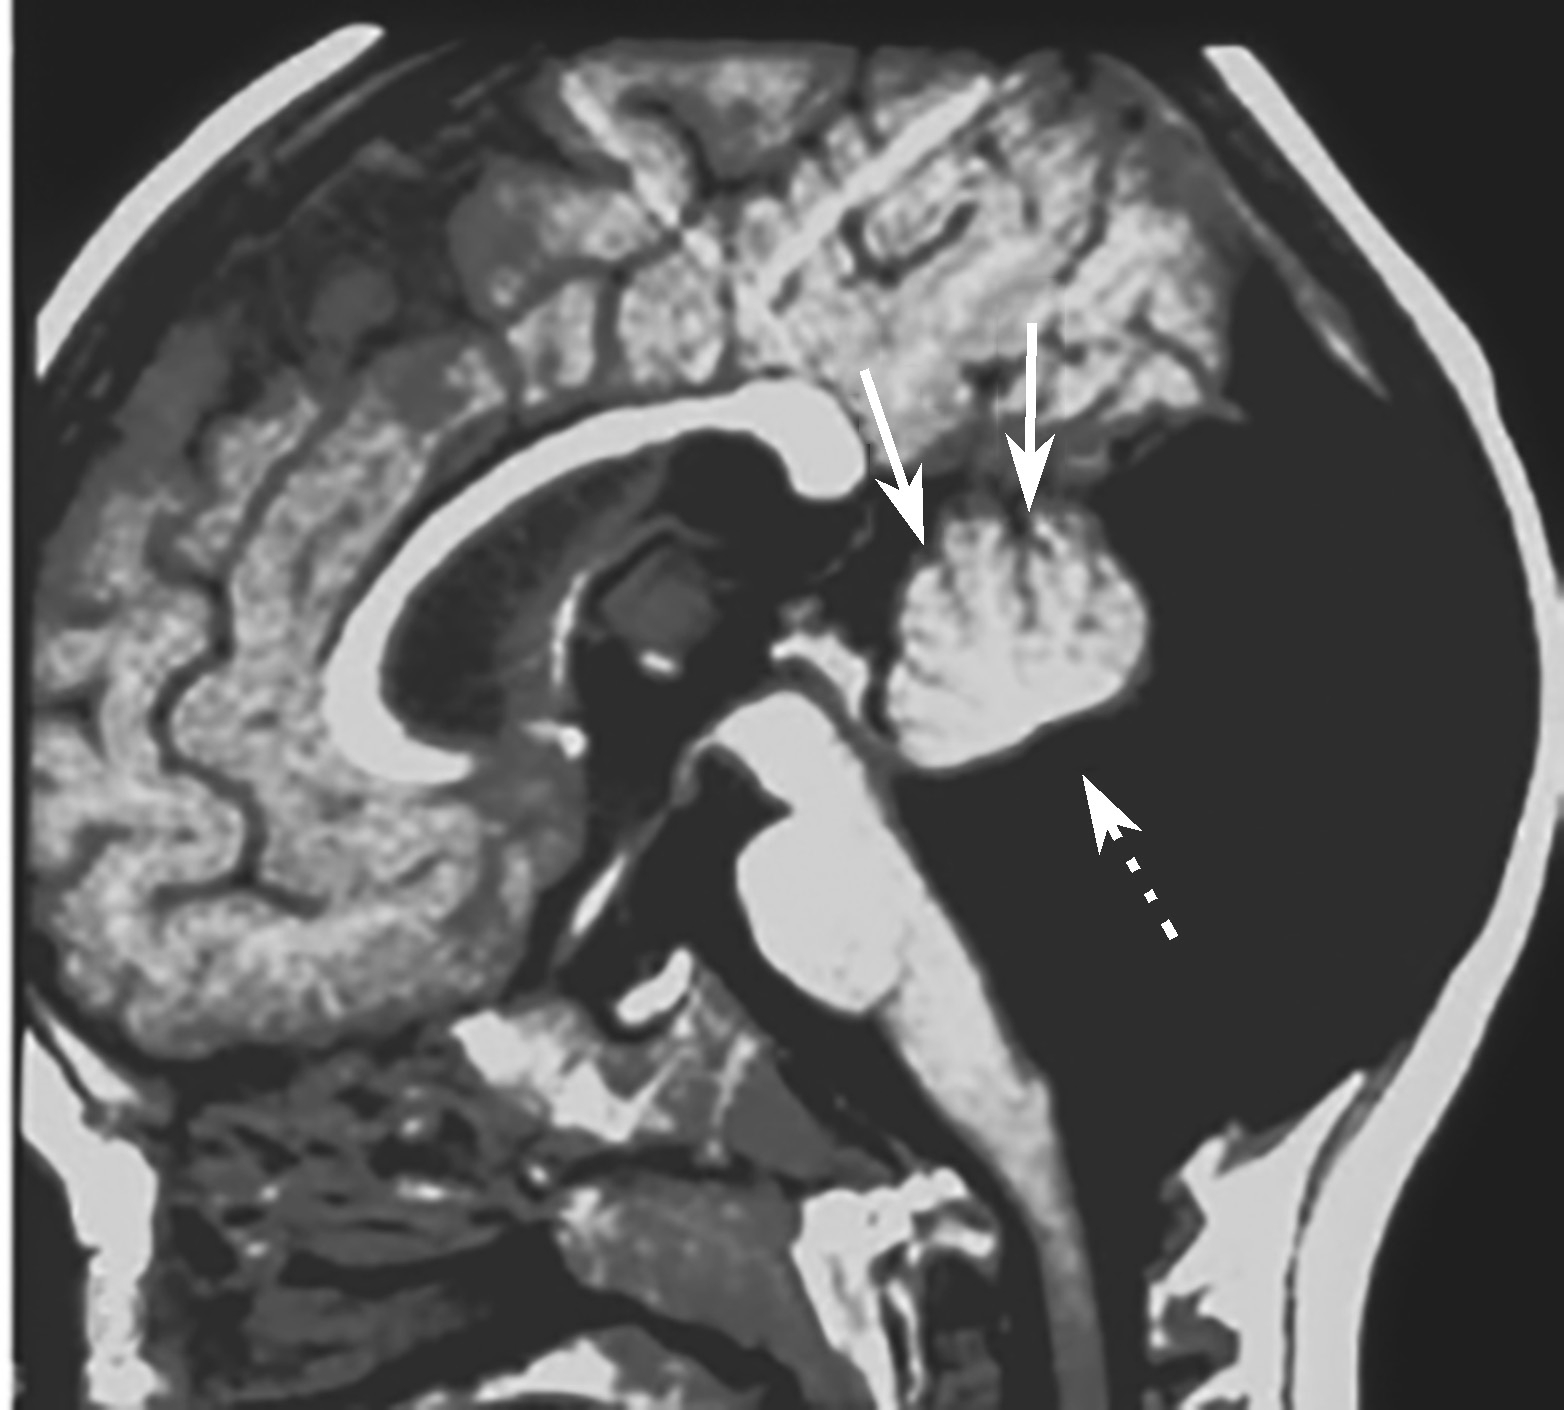

(2)MRI是诊断本病最可靠的方法,其特征表现为:

①颅后窝极度增大,伴横窦及窦汇抬高,超过人字缝;②天幕上抬超过人字缝,在冠状位和矢状位上显示尤清;③巨大的囊肿占据了颅后窝中线的绝大部分,并与扩大的第四脑室相通;④常伴有不同程度的脑积水,导水管扭结不通,小脑下蚓部缺如;⑤上蚓部被扩大的第四脑室及后方的囊腔推挤向前上方移位(图4-1-3)。需借助MRI与Blake囊肿、巨脑池、蛛网膜囊肿、单纯蚓部及小脑发育不全鉴别。

图4-1-3 患儿上蚓部向前上方移位

辅助检查:头颅MRI(图4-1-4)检查示双侧脑室系统对称性显著扩大,脑室前、后角变钝,双侧大脑半球脑实质明显变薄,脑实质内未见明确异常信号,颅后窝枕大池扩大,双侧小脑半球受压、上抬,小脑幕抬高,小脑蚓部缺如。

图4-1-4 头颅MRI检查